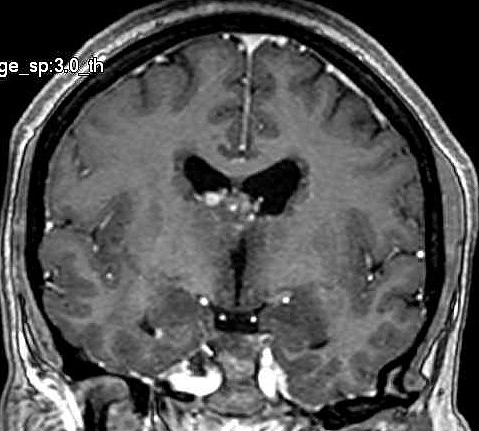

| Fem. 17a. |

| Nódulo sólido homogêneo preenchendo o III ventrículo, com limites precisos, com hipossinal em T1 e hipersinal em T2 e FLAIR, que se impregna por contraste paramagnético. Lesão menor implantada no assoalho do IV ventrículo provavelmente representa disseminação por via liquórica. |

| CORONAL, T2 | T1 COM CONTRASTE | |

| F. 17a. Tumor teratóide rabdóide atípico de III ventrículo. RM | HE | VIM, GFAP | HHF35, desmina, 1A4 | AE1AE3, EMA |